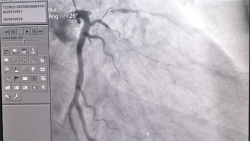

Sau một lần đi khám sức khỏe định kỳ tại Bệnh viện 108, người đàn ông hút thuốc lá lâu năm phát hiện bản thân bị hẹp khít mạn tính động mạch vành.